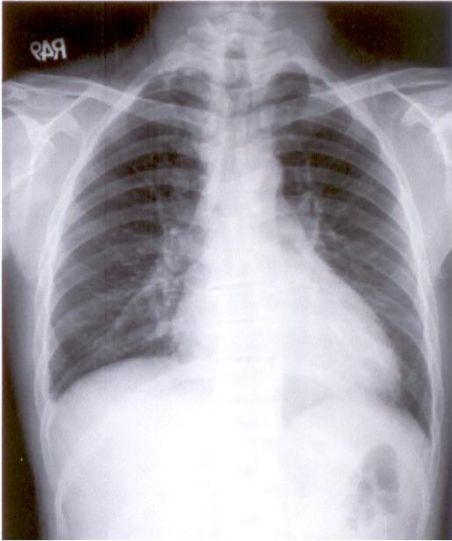

15. 病人是43歲生意人,經常出國經商,於五月十六日因有進展性呼吸困難乃至急診求醫,病人於五月三日旅行日本時突有忽冷忽熱,伴有乾咳呼吸困難及胸悶,且當時自量血壓只有90/60 mmHg¬,其後症狀稍解,乃回國休養,但在五月十四日運勳性呼吸困難逐漸轉劇.理學:血壓95/75 mmHg;心跳78/分,規則律跳;頸靜脈正常,但心臟顯著擴大,S1及S2都轉弱;都無心雜音,其他理學所見尚稱正常¬.病人有高血壓及高脂血及每天抽煙1.5包有三十年之久,且在1.5年前曾有短陣性腦缺血發作.,生化檢查:只有GOT 50u/L;GPT 25u/L;Troponin I(ng/ml), CK,(U/L)CK-MB(U/L):五月十六日 - 5.65,246,17.1;五月十七日- 3.74,190,10.1;胸部X光及心電圖 如示,請問下列何者是最有可能的診斷?

(A) 非ST上昇急性心肌梗塞症 (B) 心絞痛 (C) 心肌炎合併心肌病變 (D) 高血壓性心臟病 (E) 肺動脈血栓症